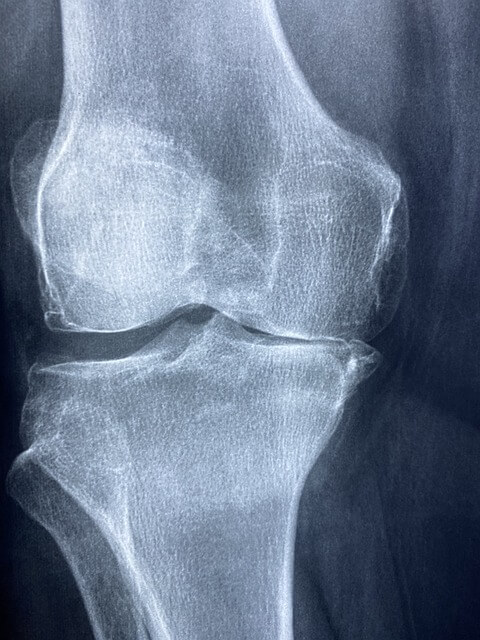

콘드로이친(Chondroitin)은 연골의 주요 구성 성분 중 하나로, 관절의 탄력성과 유연성을 유지하는 데 핵심적인 역할을 합니다. 우리 몸에서는 자연적으로 생성되지만, 나이가 들면서 점차 줄어들게 됩니다.

이 때문에 관절 통증, 무릎 뻣뻣함, 관절염 증상이 생기기도 하지요.현재는 주로 소, 돼지, 상어 연골 등에서 추출한 콘드로이친이 영양제나 건강기능식품 형태로 많이 판매되고 있어요.

1. 관절 통증 완화

콘드로이친은 관절 속 **윤활유 역할을 하는 ‘관절액(활액)’**의 농도를 유지하는 데 도움을 줍니다.

관절액이 부족하면 뼈와 뼈가 직접 마찰을 일으키며 통증과 염증이 생기게 되는데,

콘드로이친은 이 윤활유를 보충하고, 마찰을 줄여줘서 통증을 완화하는 효과가 있어요.특히 골관절염 초기 환자에게 통증 완화 효과가 입증된 바 있고, 일부 연구에선 **비스테로이드성 소염제(NSAIDs)**를 줄이는 데도 도움을 준다고 알려져 있습니다.